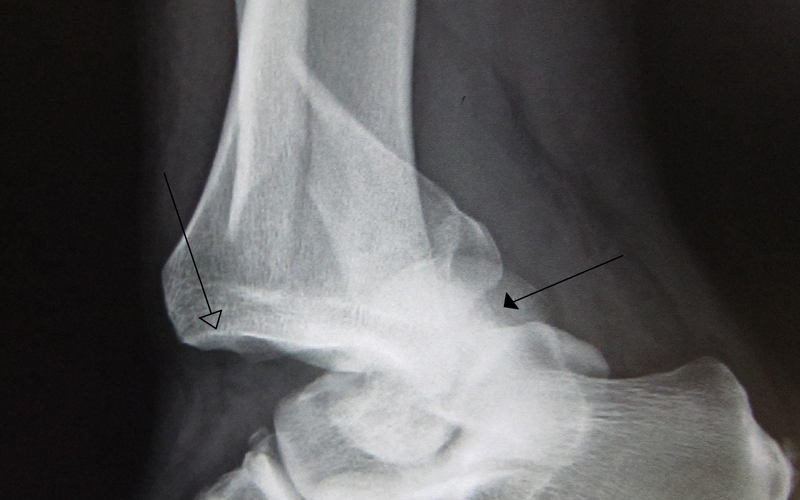

A dislocation occurs when the bones in a joint are forced out of their normal position. In the foot and ankle, dislocations often occur alongside fractures and ligament injuries, requiring expert evaluation and management.